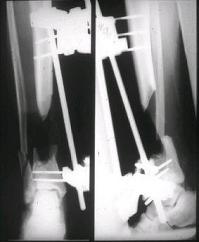

Огнестрельный дефект костей и передней группы мышц, поступил с юнилатеральным аппаратом, стабильность плохая, из раны обильное гнойное

отделяемое. #1;#2. Стержневой апп. снят, наложен апп. Илизарова, дренажно-ирригационная система промывки раны. #3; #4. После стихания инфекции,